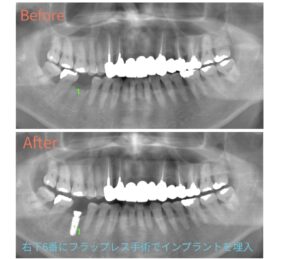

今回はインプラントのフラップレス手術の症例をご紹介します😊

こちらの患者様は、右下6番にフラップレス手術でインプラントを埋入しました。

歯ぐきを大きく切らないため、より低侵襲で行える治療方法です✨